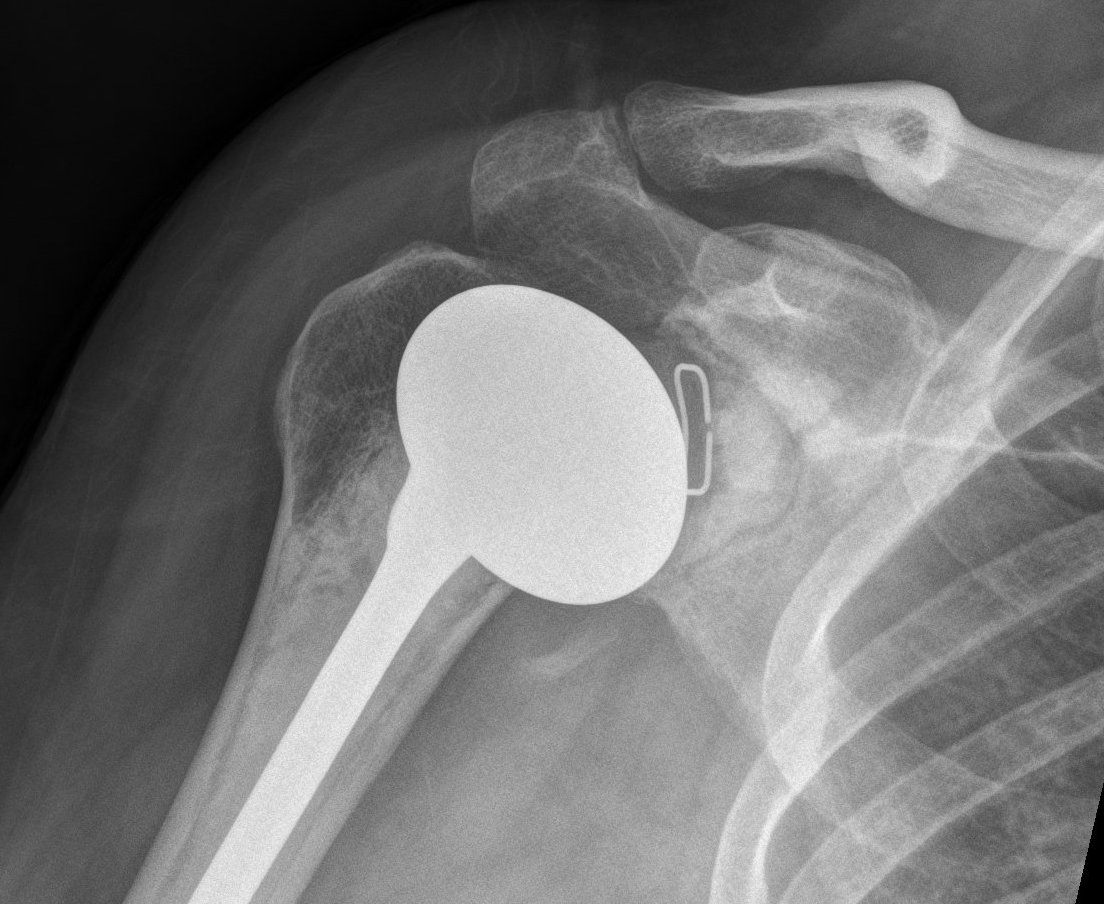

TSR Anterior Instability LateralTSR Anterior Instability AP

Posterior

Cause

- excess retroversion of glenoid or humerus

- posterior glenoid erosion

- soft tissue imbalance

TSR Posterior DislocationRevision for Posterior Dislocation TSR Combined Anterior Posterior Approach